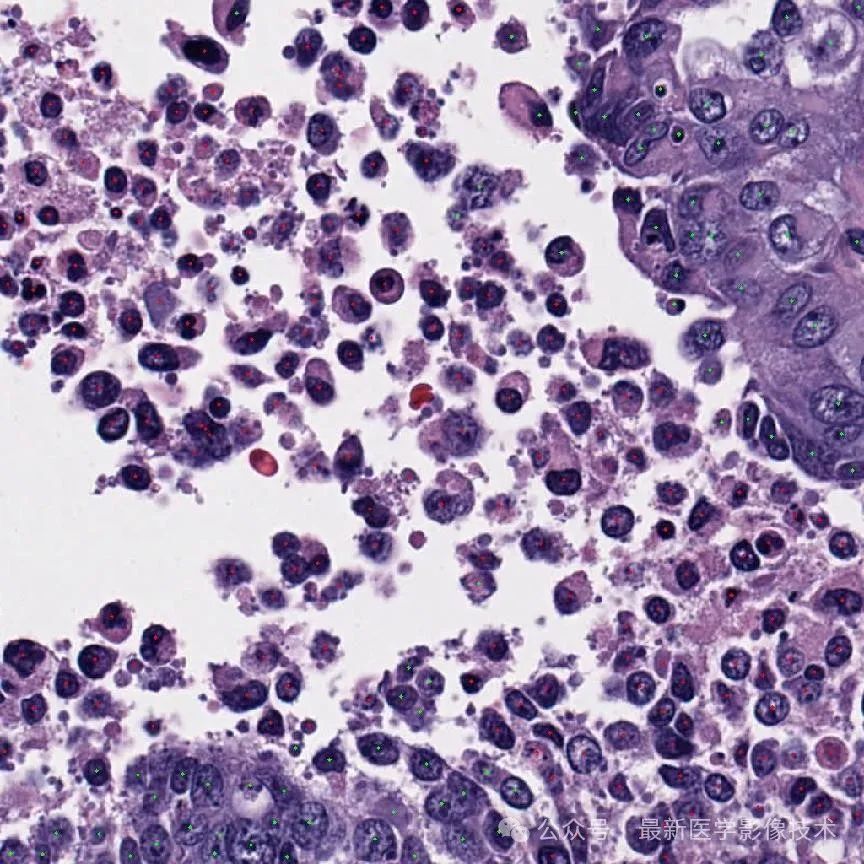

OCELOT 数据集是一个组织病理学数据集,旨在促进利用细胞和组织关系的方法的开发。该数据集由从数字扫描的整个幻灯片图像 (WSI) 中提取的小视场 (FoV) 块和大视场 (FoV) 块组成, 重叠区域。小和大 FoV 斑块分别附有细胞和组织的注释。WSI 源自公开的 TCGA 数据库,并在使用 Aperio 扫描仪扫描之前使用 H&E 方法进行染色。OCELOT数据集的每个样本由六个部分组成,其中x_s,x_l是从WSI中提取的小和大FoV斑块,y_s^c,y_l^t分别指相应的细胞和组织注释,c_x,c_y是x_s中心在x_l内的相对坐标。

下图显示了示例的可视化。

数据集的每个样本都包含两个输入块和相应的注释。左侧显示了带有组织分割注释 y_l^t 的大 FoV 块 x_l,其中绿色表示癌症区域。右侧显示带有细胞点注释 y_s^c 的小视场块 x_s,其中蓝色和黄色点分别表示肿瘤和背景细胞。红色框表示 x_s 相对于 x_l 的大小和位置。请注意,对于每个样本,x_s 和 x_l 是重叠的,即 x_s 存在于 x_l 内部。然而,x_s 在 x_l 上的相对位置因样本而异。

细胞检测任务受益于细粒度的空间信息,可以更好地捕获详细的细胞属性(例如边界、形状、颜色和不透明度)。相比之下,组织分割需要更大的背景才能更好地理解整体结构信息。因此,将x_s(细胞检测)和x_l(组织分割)的FoV大小分别定义为1024×1024和4096×4096像素,分辨率为0.2微米每像素(MPP)。最后,将大 FoV 块和组织注释 (x_l, y_l^t) 下采样4倍,得到1024x1024像素的大小。